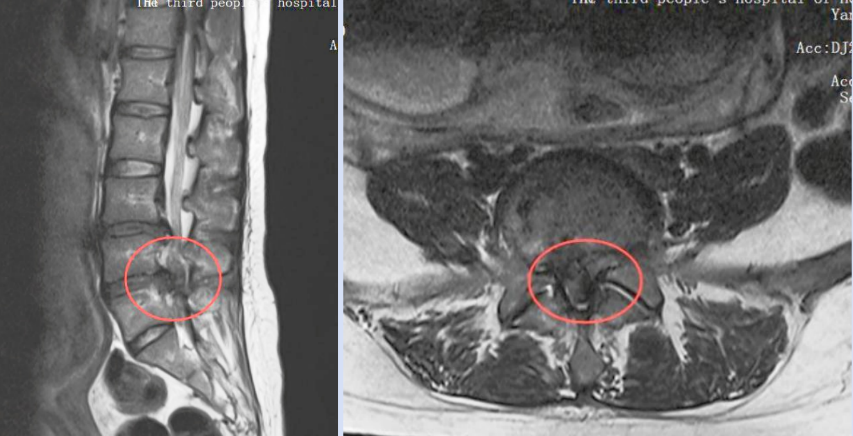

当地医院诊断后,结果令全家心弦紧绷——这不是普通的孕期不适,而是由严重腰椎间盘突出引发的 「马尾神经综合征」。

麻醉手术部与超声科联手,采用「全程超声可视化引导」进行精准定位与麻醉,避免了传统脊柱微创手术中必需的 X 射线(C 臂)透视;

脊柱微创外科则运用局麻下的微创技术,以最小创伤,精准解除神经压迫。

在多学科团队的精密配合下,李女士接受了超声引导下的腰椎微创手术。